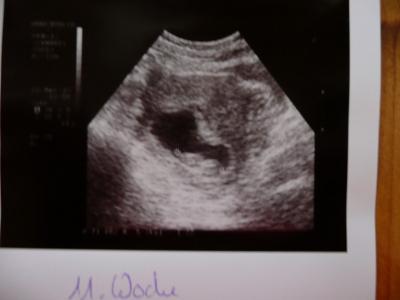

guten morgen ihr lieben, vielen dank fürs daumen drücken hier ein foto von unserem 3. projekt allen ein schönes sonniges wochenende kussi an alle sonja

Bild zu projekt erika - Forum für November - Mamis